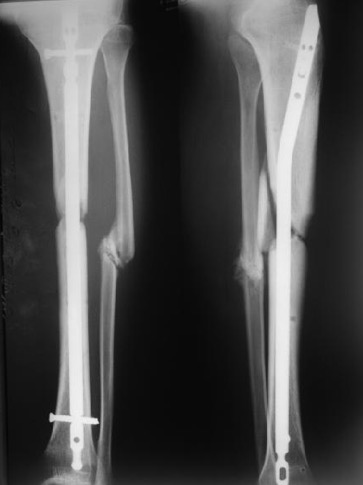

Вложение не в текстовом формате было извлечено&hellip;

Имя     : Снимок экрана 2018-03-31 в 8.38.51.jpg

Тип     : image/jpeg

Размер  : 30924 байтов

Описание: отсутствует

Url     : http://weborto.net:8080/pipermail/ortho/attachments/20180331/6be0b812/attachment-0004.jpg